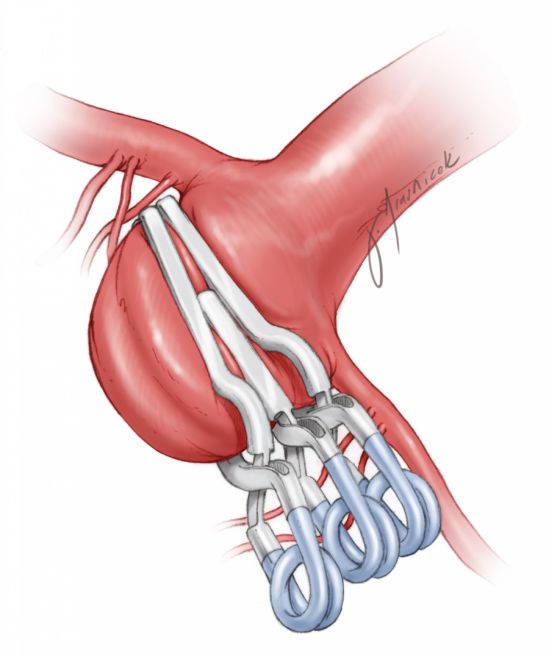

图16:以向下堆的串联方式夹闭基底动脉分叉部动脉瘤很有优势。开窗夹放置在动脉瘤远端,夹闭瘤颈远端的大部分。第二个简单型瘤夹放置在开窗夹近端,夹闭瘤颈的残余部分。夹闭瘤颈的同时,避开了流出动脉。